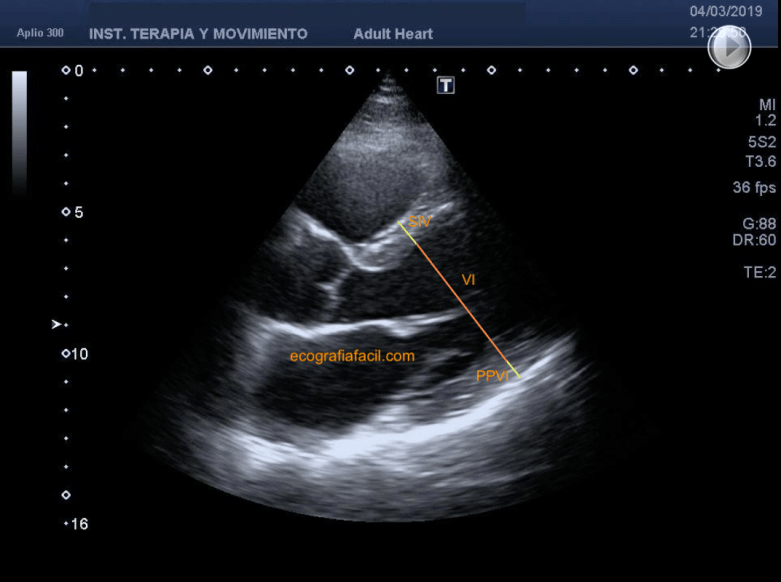

Un poco más allá en el tiempo, veremos que el diámetro del VI es máximo al final de la diástole, así que aquí volveremos a medir el diámetro del VI en el mismo punto anatómico que lo hicimos anteriormente. Además, podemos medir el espesor del septo interventricular y de la cara lateral-inferior del VI (fig 12).

A little further in time, we will see that the diameter of the LV is maximum at the end of diastole, so here we will again measure the diameter of the LV at the same anatomic point as we did previously. In addition, we can measure the thickness of the interventricular septum and the lateral-inferior aspect of the LV (fig 12).